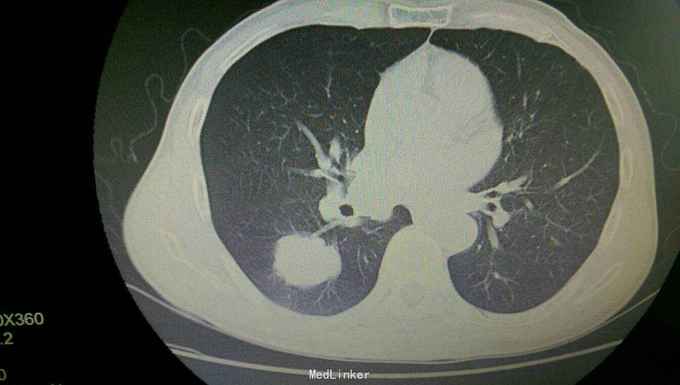

患者入院后,拟行左颌下肿块切除,在术前检查,术前准备时,常规胸片发现右侧肺部肿块,进一步行颈部及胸部ct检查,提示左颌下淋巴结肿大,转移性可能。右下肺周围性肺癌伴右肺门及纵膈多发淋巴转移考虑。决定先行左颌下肿块切除,明确诊断。术后病理示:左(左颌下腺)淋巴结转移性癌,来源首先考虑为肺。患者及家属考虑为晚期肿瘤,拒绝进一步手术治疗及化疗,下颌部切口愈合拆线后,出院。

患者出院后,门诊服中药治疗,定期复查。 讨论:患者因左颌下肿块前来就诊,术前检查发现肺部肿块,一元论考虑,应为肺部肿瘤转移所致。而且手术后病理亦证实。关键当下颌部出现肿块,应考虑肿块性质的鉴别。1.应考虑颌下肿块与颈部淋巴结的鉴别,尤其是无痛性肿块,要和淋巴结核及肿瘤等鉴别。2要和周围组织的肿瘤如甲状腺,鼻咽癌等浸润转移鉴别。3.要考虑纵膈,肺等远处转移。该患者为右下肺肿瘤已向纵膈及颈部,颌下转移,但患者临床表现仅有左颌下肿块,无胸闷气急,无咳嗽咳痰,虽ct检查发现纵膈及颈部多发淋巴结肿大,患者却无上腔静脉回流受阻,颈部浅表淋巴结未能扪及。该病例提示我们,当患者颈部出现肿块,应仔细检查,多些鉴别,以免漏诊。